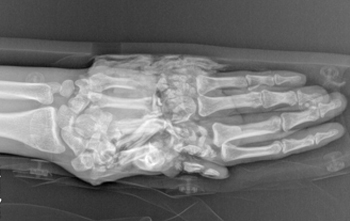

科室在肢體嚴重撕脫創(chuàng)傷、復(fù)雜斷指(肢)再植、各類型游離足趾移植拇手指再造或組合再造、游離皮瓣修復(fù)四肢缺損創(chuàng)面等方面取得顯著成績,受到了省內(nèi)外專家和廣大患者高度評價。近年來,科室不斷拓寬診治范圍,深耕手病?疲珉烨恃、周圍神經(jīng)損傷、肌腱修復(fù)等,在腕關(guān)節(jié)鏡微創(chuàng)治療方面取得了長足的進步,形成了自己的治療特色。

◎ 斷指(肢)再植 ◎ 游離足趾移植拇手指再造或組合再造

◎ 手部疾。弘烨恃、周圍神經(jīng)損傷、肌腱修復(fù)等

擅長:四肢顯微修復(fù)及功能重建;特殊類型斷指(肢)再植,小兒斷指再植;拇手指全型再造;小兒手足先天性畸形矯形、燒傷瘢痕整形;四肢骨缺損、手部各種腫瘤、周圍神經(jīng)損傷的診治;腱鞘炎、周圍神經(jīng)損傷、肌腱修復(fù)等;腕關(guān)節(jié)鏡的微創(chuàng)治療